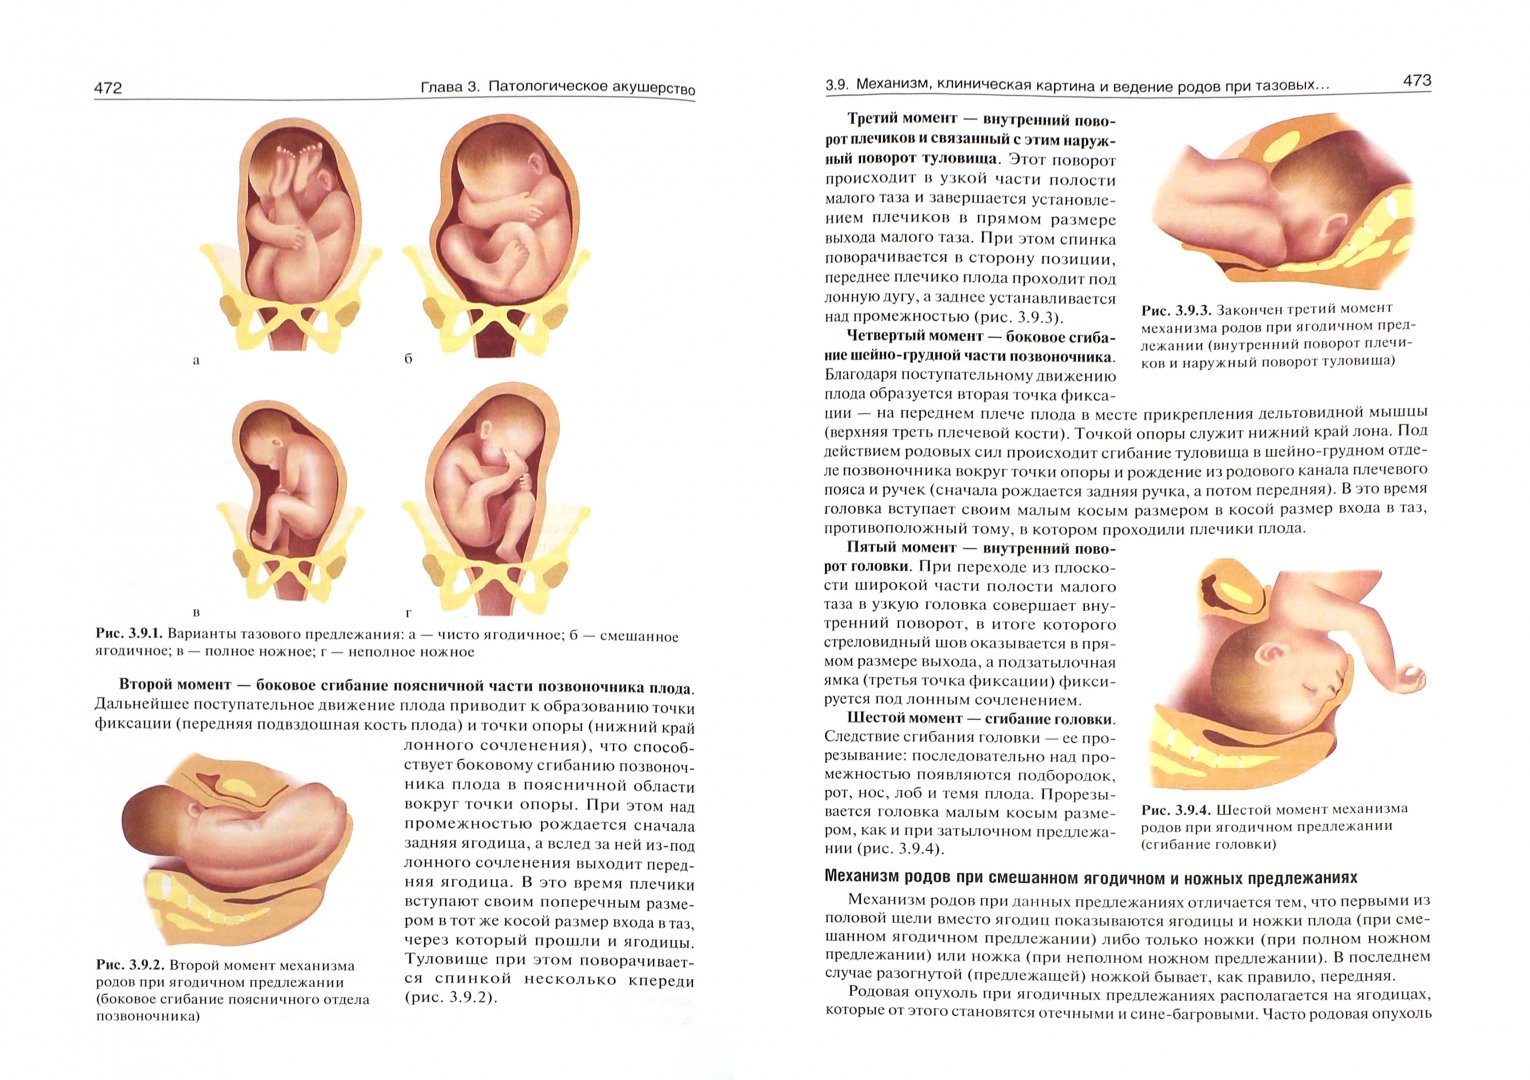

Breech.webp)

Живот с ягодичным предлежанием

Рождение ребенка в тазовом предлежании

Первый момент биомеханизма родов при тазовом предлежании